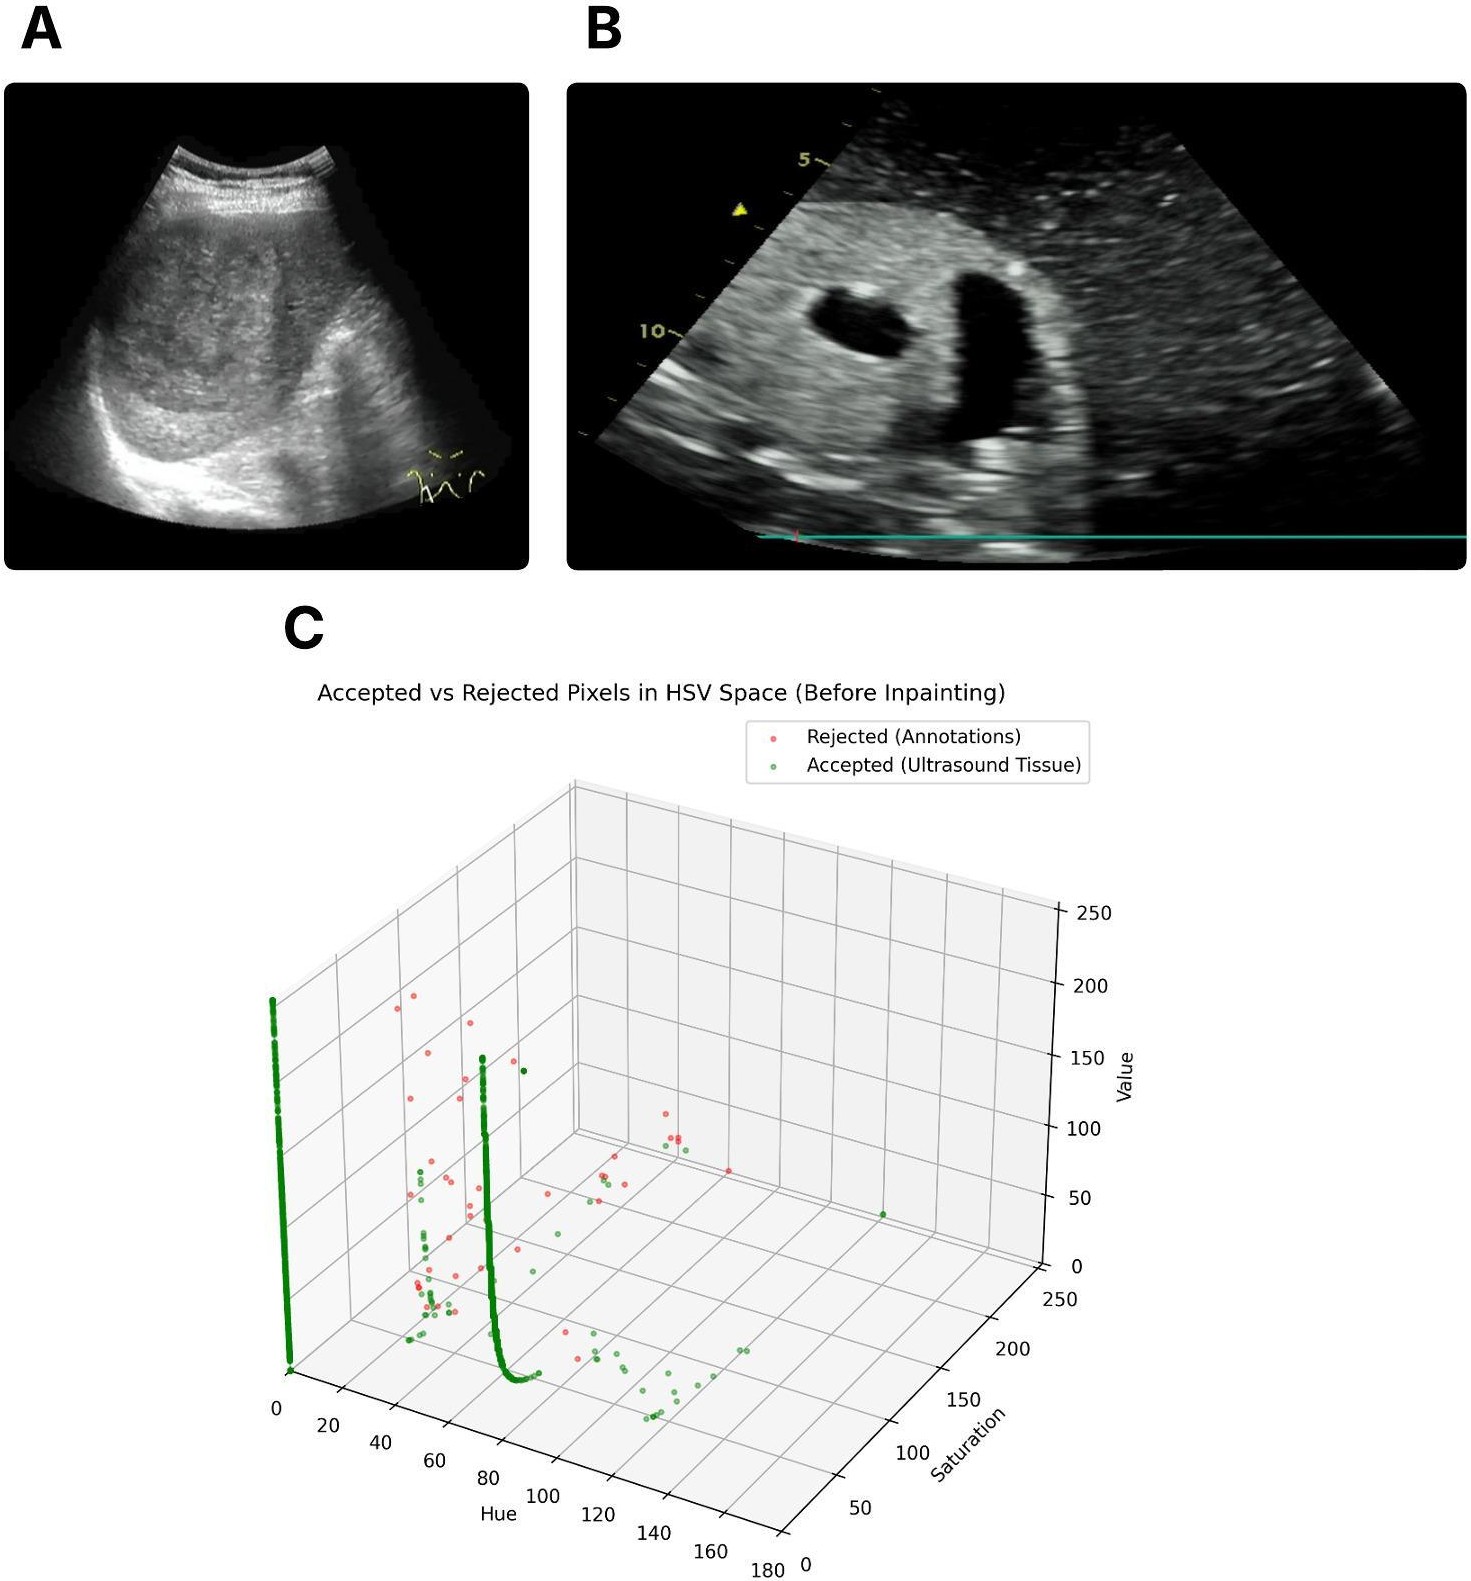

Refer to caption

Figure 2: US images of two scans from AUL dataset(A) and Cactus dataset (B), and visualization of accepted vs. rejected pixels in HSV color space before inpainting (C). Accepted pixels correspond to US tissue, while rejected pixels represent annotation overlays.

As a first step, these annotations were removed because many datasets contain overlaid text or graphical markers, such as labels, arrows, lesion outlines, and measurements, shown in Fig. 2. We implemented a unified detection and inpainting framework to automatically identify and suppress these annotations. Text elements were localized in grayscale images using Tesseract OCR (Optical Character Recognition), and bounding boxes were converted into binary masks. To detect weak or low-contrast annotations, contrast-limited adaptive histogram equalization (CLAHE) was applied to the luminance channel of the CIELAB colour space to improve visibility before detection. Colour-based annotations (including highlighter strokes and ink) were segmented in the HSV colour space, with Fig. 2C showing a 3D visualization of pixel distribution in HSV space, and highly saturated pixels are clustered using K-Means clustering. Grayscale annotations (such as pencil marks and underlines) were separated using Canny edge detection, followed by contour extraction. Masks generated from the text, colour, and grayscale channels were combined into a unified annotation mask, which was then refined using morphological closing and opening operations. Finally, a Navier-Stokes-based [67] inpainting algorithm (implemented in OpenCV) was applied to reconstruct the background structure within the masked region. This procedure effectively removed diverse annotation types while preserving underlying US information (Fig. 3 - example of annotation removal).